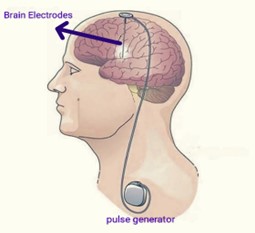

1st DBS device programming in Uttarakhand for Parkinsons disease done by Dr Jyoti Gautam at Graphic Era Hospital.

Deep brain stimulation (DBS) Is process of giving electrical impulses via implanted electrodes to specific brain areas. The implanted electrodes are connected with wire to